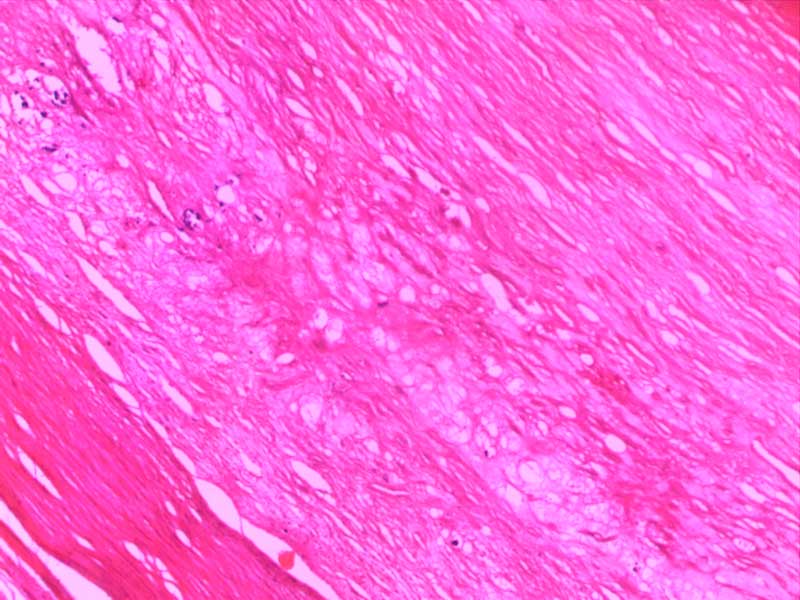

神经鞘瘤-10倍

肾透明细胞癌-10倍

肾细胞水肿-4倍

粟粒性肺结核

透明血栓-10倍

纤维肉瘤10-倍

纤维素性胸膜炎

小叶性肺炎-10倍-(2)

新月体肾炎-(2)

异物性炎-10倍

主动脉粥样硬化-4倍

主动脉粥样硬化-10倍